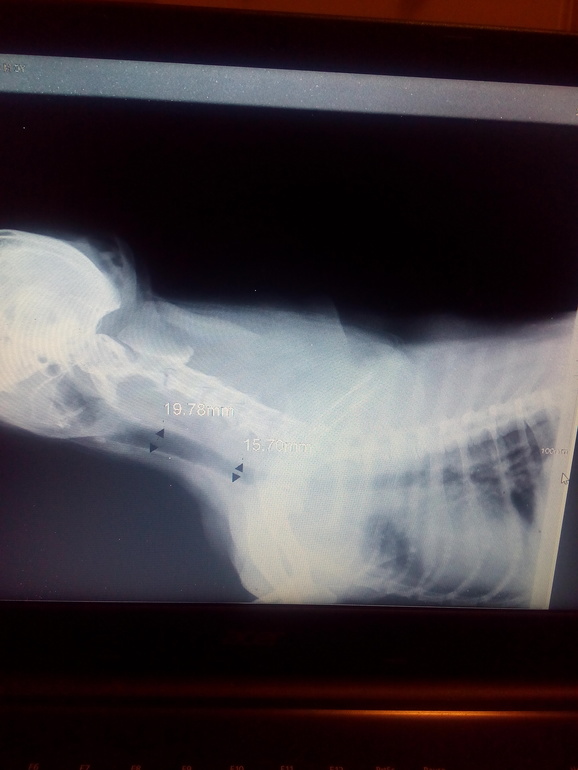

Новости сообществаДоброго времени суток! Столкнулась с проблемой, которая не даёт нам покоя вот уже практически 4 месяца. Очень надеюсь, что на сайте есть знающие люди, может быть ветеринары, которые что то подскажут, посоветуют.. Взяли собаку из приюта в июле, пара месяцев было все идеально. С сентября собака закашляла. В ветеринарную клинику начали ездить как на работу, каждые пару недель. Кровь сдавали два раза, все в норме, делали рентген, сердце в норме, инородных предметов нет. В бронхах по рентгену усилен рисунок, это своими словами, как я поняла, но врач сказал что это от того что собака кашляет, ничего критического, якобы накашляла. За эти месяцы мы перепили тонны лекарств. Бромгексин сироп, месяц антибиотик синулокс, пока пили, были улучшения, перестали все началось по новой. Назначили Эуфиллин, его пьют даже астматики, помогал плохо, Алмонд, так же для расширения бронхов, вообще результатов не даёт. Врачи из хорошей клиники, вытягивают таких безнадёжных животных, что удивляешься, выкачкой денег они не занимаются, а вот нам помочь не могут, открытым текстом от нас уже откащываются, говорят что не видят причины кашля. Собака кашляет только дома, выходим за порог, кашель сходит на нет. Отказалась от сухого корма, перевела на натуральное питание. Купили увлажнитель воздуха, с ним вроде полегче, но кашель постоянно присутствует, особенно по утрам и когда собака встаёт после лежания, а лежит она 90% всего времени, но это только дома, на улице активна. Температуры не наблюдала у нее. Куда бежать, к кому обращаться, я уже как зомби, а помочь некому. Очень буду признательна, если кто то что то подскажет, или может посоветует ветклинику в Нижнем Новгороде, или врача, чтоб не нарваться на очередную выкачку денег. Нужен грамотный специалист!!!